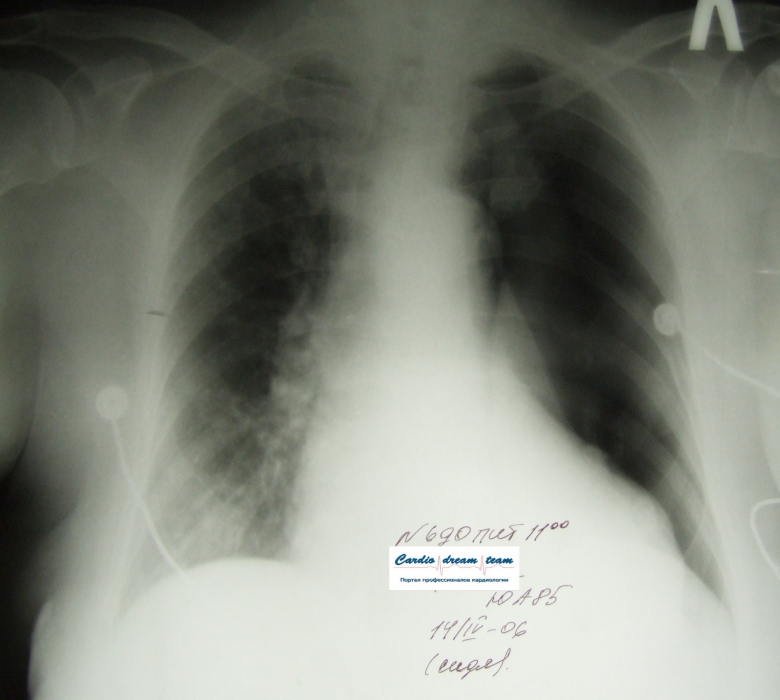

ИССЛЕДОВАНИЕ ОРГАНОВ ГРУДНОЙ КЛЕТКИ Дата 01-ОКТ-15 время 11.30 ОПИСАНИЕ: Проведена рентгенография органов грудной клетки в прямой проекции, положение сидя, условия ПИТ, Р-контроль Легочные поля: Справа легкое расправлено не полностью, апикально до 3го ребра прослеживается свободный газ в плевральной полости. Тень дренажа справа. Тень подключичного катетера в проекции ВПВ. Легочный рисунок: сгущен справа в прикорневой зоне, диффузно деформирован Корни: малоструктурны, обогащены Синусы: нечеткие Сердце: широко лежит на диафрагме (позиционно) ЗАКЛЮЧЕНИЕ: Течение правостороннего пневмоторакса, положительная Р-динамика. Состояние дренирования правой плевральной полости. Р-признаки полнокровия сосудов МКК. Пневмосклероз. Р-контроль .────────────────────────────────────────────────────────────────────── ИССЛЕДОВАНИЕ ОРГАНОВ ГРУДНОЙ КЛЕТКИ Дата 02-ОКТ-15 время 1015 ОПИСАНИЕ: